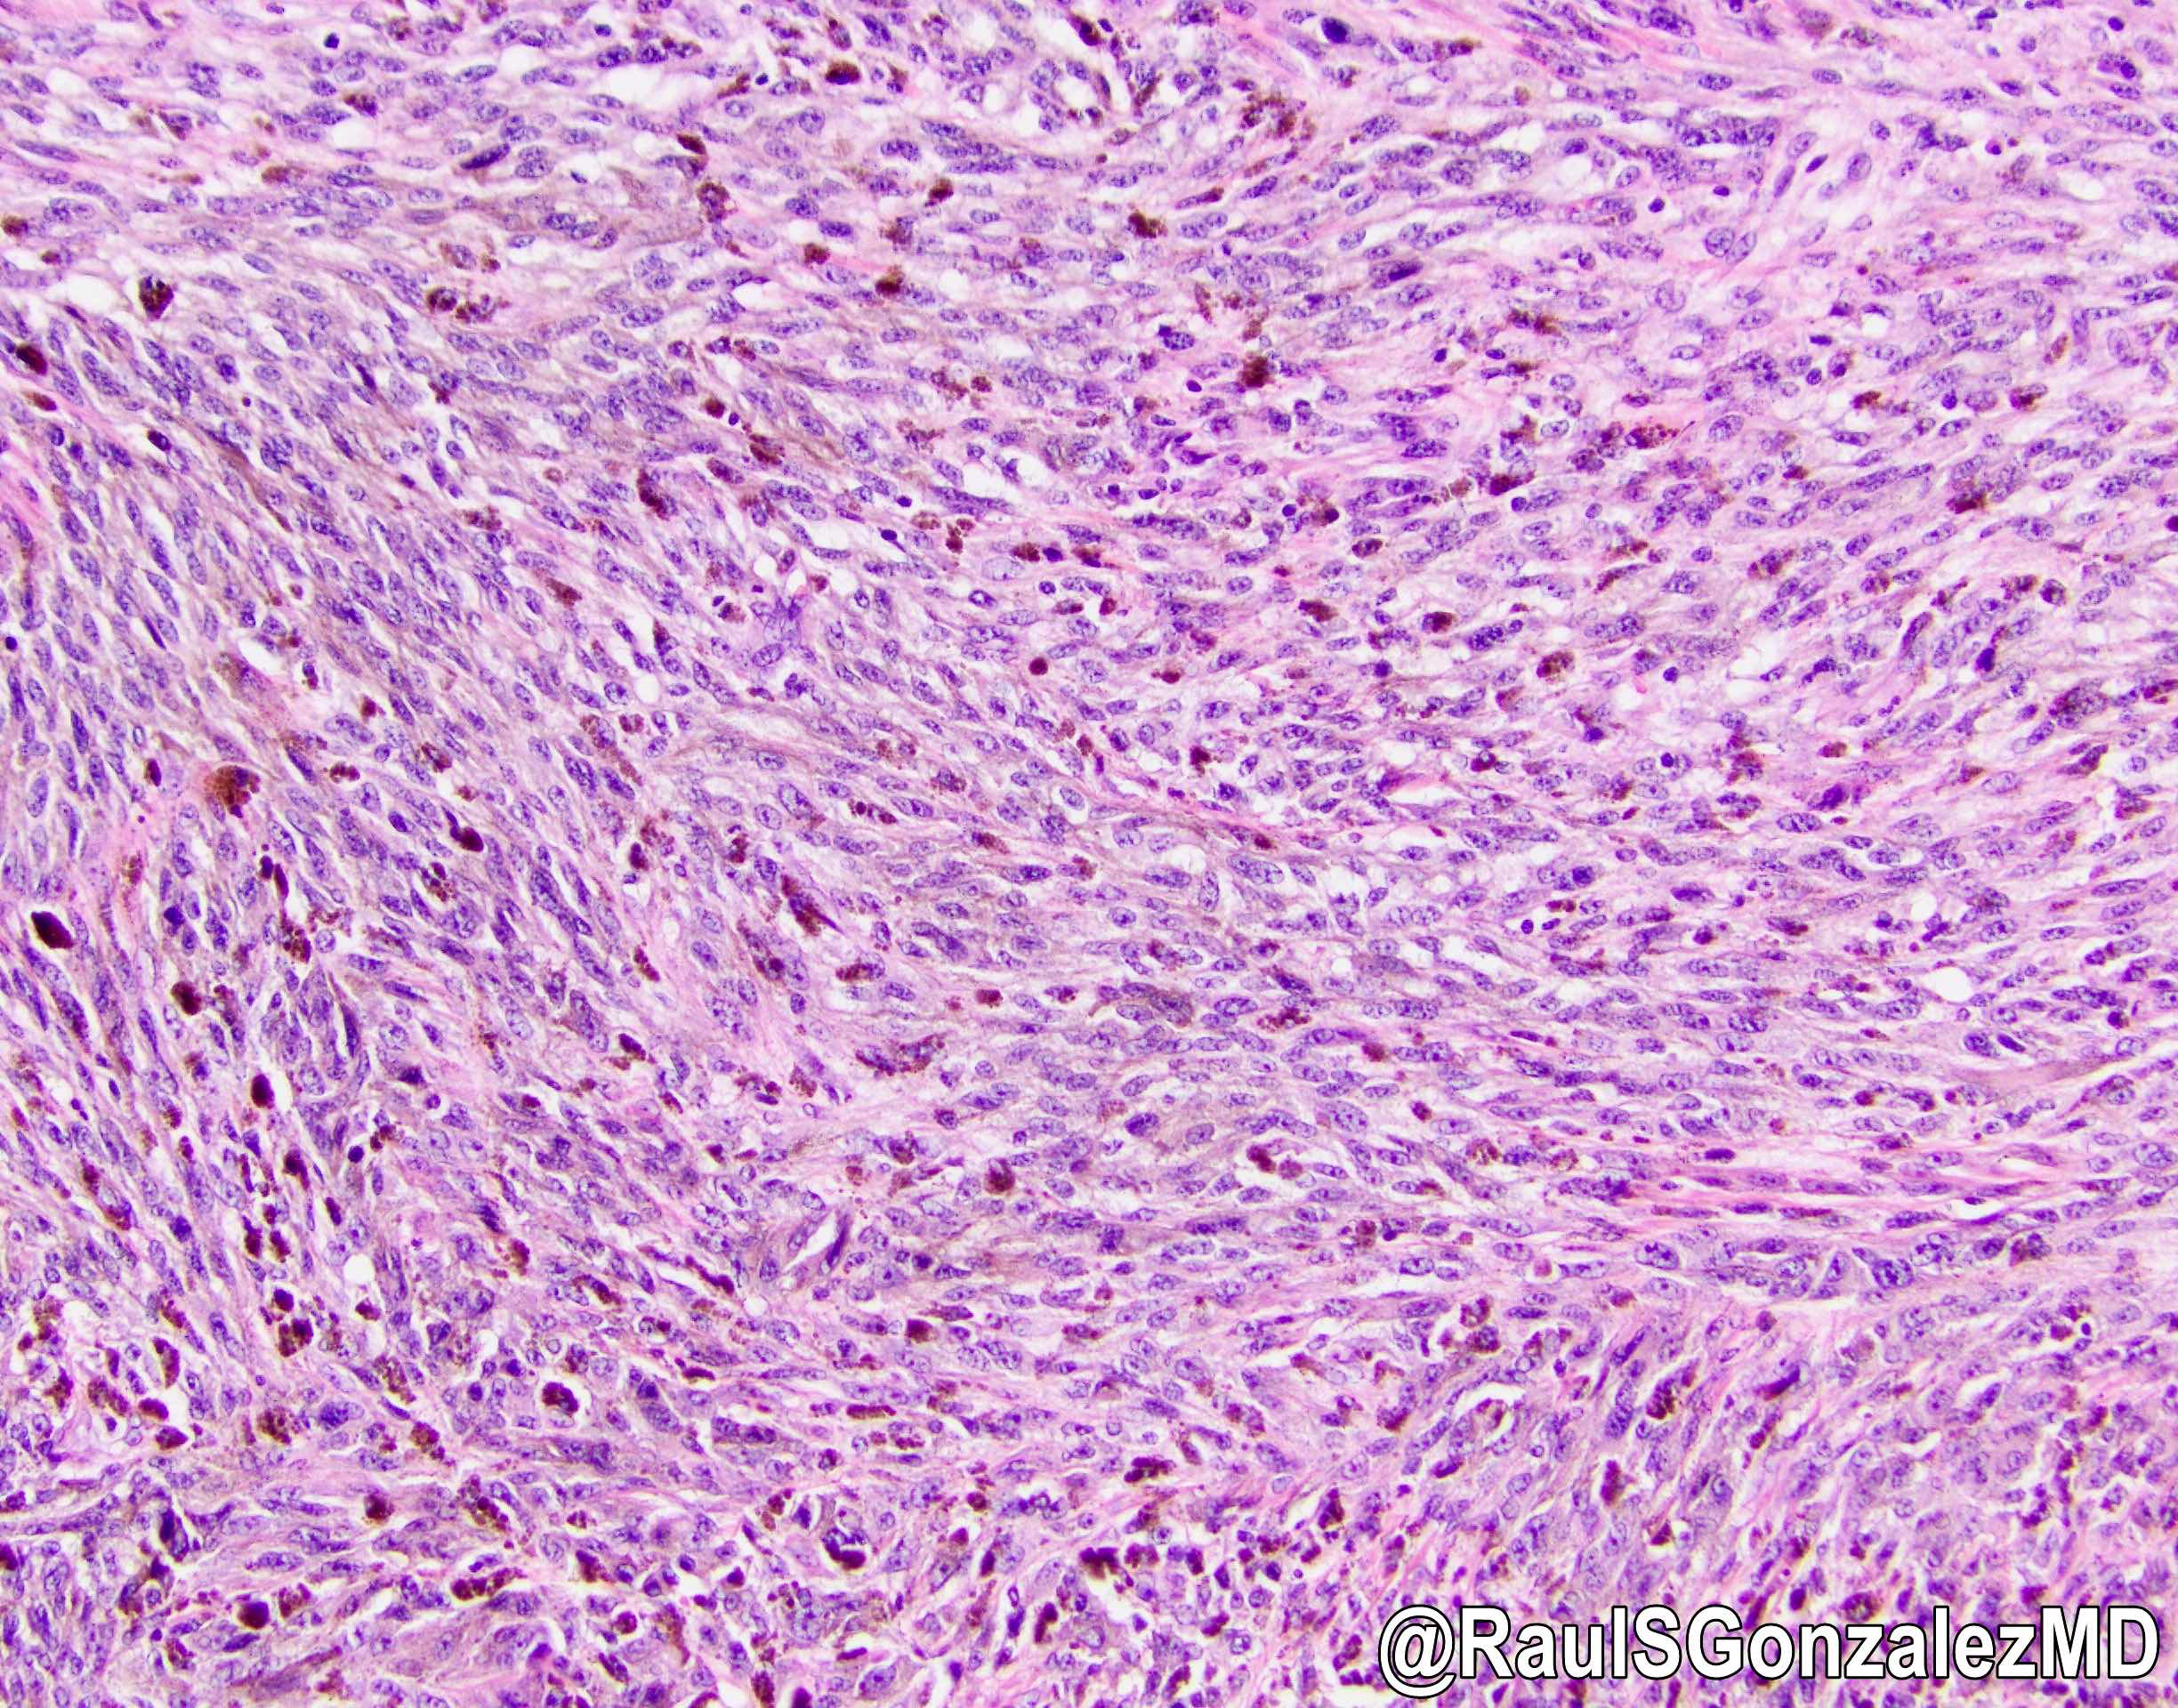

Microscopic (histologic) description

- Mostly epithelioid tumor cells with at least focal melanin pigment (Mod Pathol 2019;32:957)

- Associated melanoma in situ component (junctional melanocytic activity / junctional melanocytic component / tumor nests at the epithelium - lamina propria junction / horizontal tumor spread in the basal layer of the epithelium) and melanocytosis / melanosis (Mod Pathol 2019;32:957, Ann Thorac Surg 2013;96:1002)

Microscopic (histologic) images

A. Junctional melanocytic activity (shown in the picture) suggests a primary malignant melanoma of the esophagus